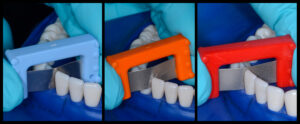

The Bioclear (Tacoma WA USA) BT kit used in case one is shown in Figure 18 with the four important components: small and large BT matrices in four different and color-coded emergence profiles, dual color disclosing solution, the black triangle sizing gauge, and the TruContact sanders. Additional materials and instruments are explained in the body of the article.

First, the Black Triangle gauge is inserted buccal-lingually below the contact to assess the mesio-distal size of the black triangle. (Fig 19) The gauge will bind at one of the four colors. In this case the gauge binds in the pink zone Then a pair of correspondingly color-coded Black Triangle matrices are tried in for each embrasure. Before the rubber dam is placed, the TruContact sanders are used to groom the contact area to remove calculus and to lighten the tension of the contact areas to allow the matrices to seat fully. (Fig 20) Once the rubber dam is placed, the teeth are disclosed (Fig 21) and then blasted with an air/water/abrasive slurry of aluminum try-hydroxide (Fig 22) (Bioclear Blaster). The 37% phosphoric acid used to condition the teeth does not remove the soft, sticky biofilm that covers the tooth. It is therefore imperative that the teeth be aggressively cleansed before acid-etching.

Additionally we now understand that the protein pellicle that coats the tooth must be removed to achieve an ideal bond. The interproximal area is extremely difficult to access with scalers and prophy cups and is of course the exact area that we are attempting to bond to when treating black triangles. In general, the BT gauge will match the profile of the corresponding matrices, but in this case the more aggressive emergence profile matrix, or yellow BT matrices are chosen because of the unique shape of the teeth even though the gauge suggested the pink color. (Fig 23)